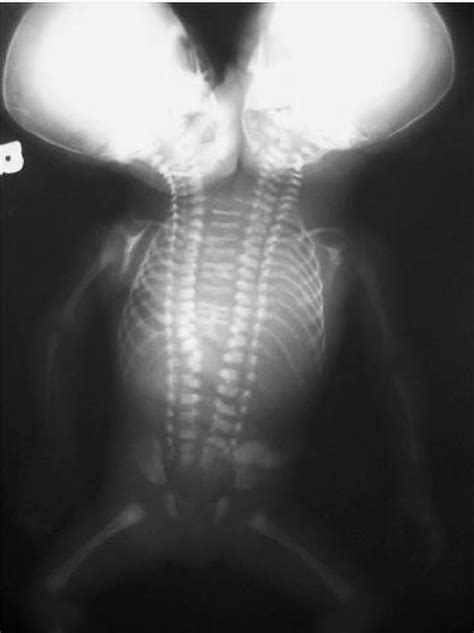

Following birth, a thorough physical examination and additional imaging studies are performed to confirm the diagnosis and assess the overall health of the twins. This may involve X-rays, CT scans, or echocardiograms to evaluate the structure and function of the internal organs. The medical team carefully assesses the extent of the conjoinment, identifies any potential complications, and develops a comprehensive treatment plan. Genetic testing may also be performed to look for any underlying genetic abnormalities that could contribute to the condition.

At its core, dicephalic parapagus refers to conjoined twins who have two heads on one body. Think of it as a single body with two separate heads and necks . The extent of the shared body can vary, ranging from sharing just the upper torso to sharing almost the entire body down to the pelvis. This variation significantly impacts the organs that are shared and how they function. For example, the twins might share a heart, liver, or intestines, each of which presents unique medical challenges. Understanding the specific anatomical arrangement is crucial for managing the health and well-being of these individuals.